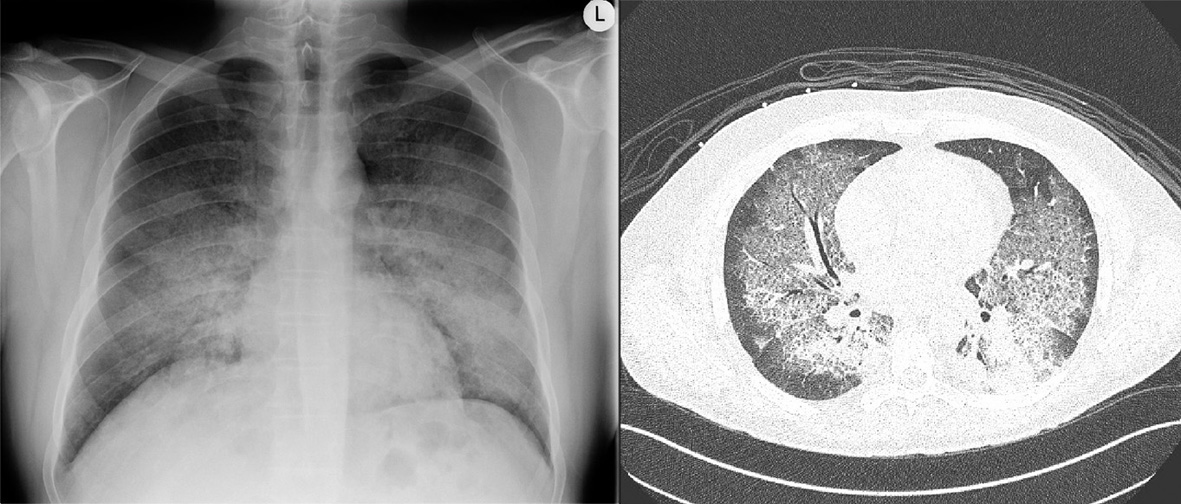

Initial laboratory testing demonstrated anemia, acute kidney injury with hematuria (Table 1). Chest X-ray and computed tomography (CT) of the chest revealed bilateral ground glass opacities consistent with diffuse alveolar hemorrhage (Fig. 1). CT scan of the sinuses only found minimal thickening of his maxillary, frontal, ethmoid, and sphenoid sinuses.

![]() Click for large image | Figure 1. Chest X-ray and computed tomography of the chest demonstrating ground glass opacities consistent with diffuse alveolar hemorrhage in anti-glomerular basement membrane antibody disease. |